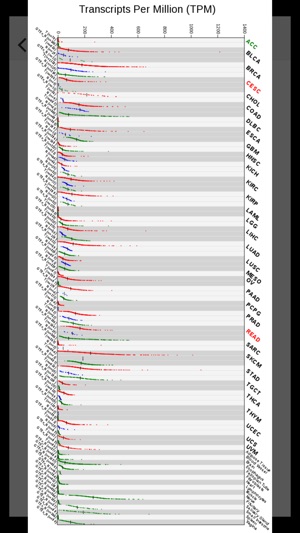

This GE-mini APP is designed to exhibit gene expression profiling of a given gene over many tissue types including tumors. The underlying data are based on RNA Sequencing results from both TCGA and GTEx after they are normalized and integrated. The current version, based on the September 2015 release of TCGA and the phs000424.v6.p1 release of GTEx, contains >19,000 total samples across 33 cancer types and 53 normal tissue types.